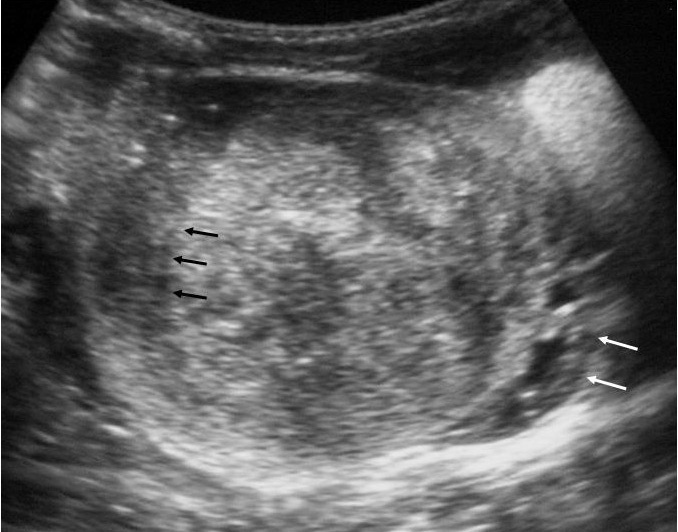

Los pacientes con diagnóstico histológico de tumor quístico multilocular (n = 7) tenían entre 5 meses y 12 años, siendo 4 de ellos varones y 3 mujeres. La clínica inicial fue la de masa abdominal palpable en 5, hematuria en uno y dolor abdominal en el paciente mayor. Se identificaron masas renales bien definidas que presentaban un aspecto quístico, con múltiples loculaciones separadas por septos que mostraban discreto realce (figs. 3 y 4). En un paciente se encontraron focos de blastema en las paredes de los septos en el estudio histológico.

Fig. 3. Tumor quístico multilocular. (A) Ecografía abdominal. Corte renal longitudinal. Masa renal heterogénea con predominio de áreas anecoicas. (B) Tomografía computarizada abdominal con contraste intravenoso. Corte sobre polo superior renal izquierdo. Masa de aspecto multiquístico que presenta zonas de parénquima renal sano entre las formaciones quísticas.

Los estudios radiológicos muestran una masa de gran tamaño, encapsulada, con múltiples quistes no comunicantes, que pueden herniarse hacia la pelvis y el uréter y cuyos septos presentan un realce irregular bajo o moderado4,8,9.